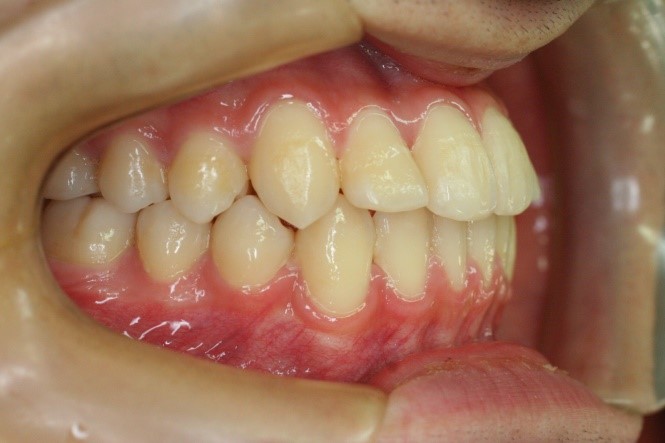

症例02|20代の男子

前歯部の反対咬合の症例

上下の前歯が反対咬合を主訴として来院されました。通常通り検査を行い「反対咬合」と診断されました。

治療計画

下の犬歯から後ろの歯をまずは後方に移動して、その後に上下の歯並びを綺麗に並べて前歯部の咬み合わせを改善することにしました。

矯正の種類

カリエールディスタライザー、上に裏側、下に表側のセラミック(白い矯正装置)

治療前

• 右側

治療後

コメント

治療前の写真を治療後の写真を比べると、鼻の下がくぼんでいたのが改善されて口元が綺麗になった事が解ります。また歯並びは綺麗に並び上の歯が前に出て下の歯が後ろに移動して歯がしっかりと咬み合っています。

患者様に協力いただけたため、2年の治療期間で終了することができました。